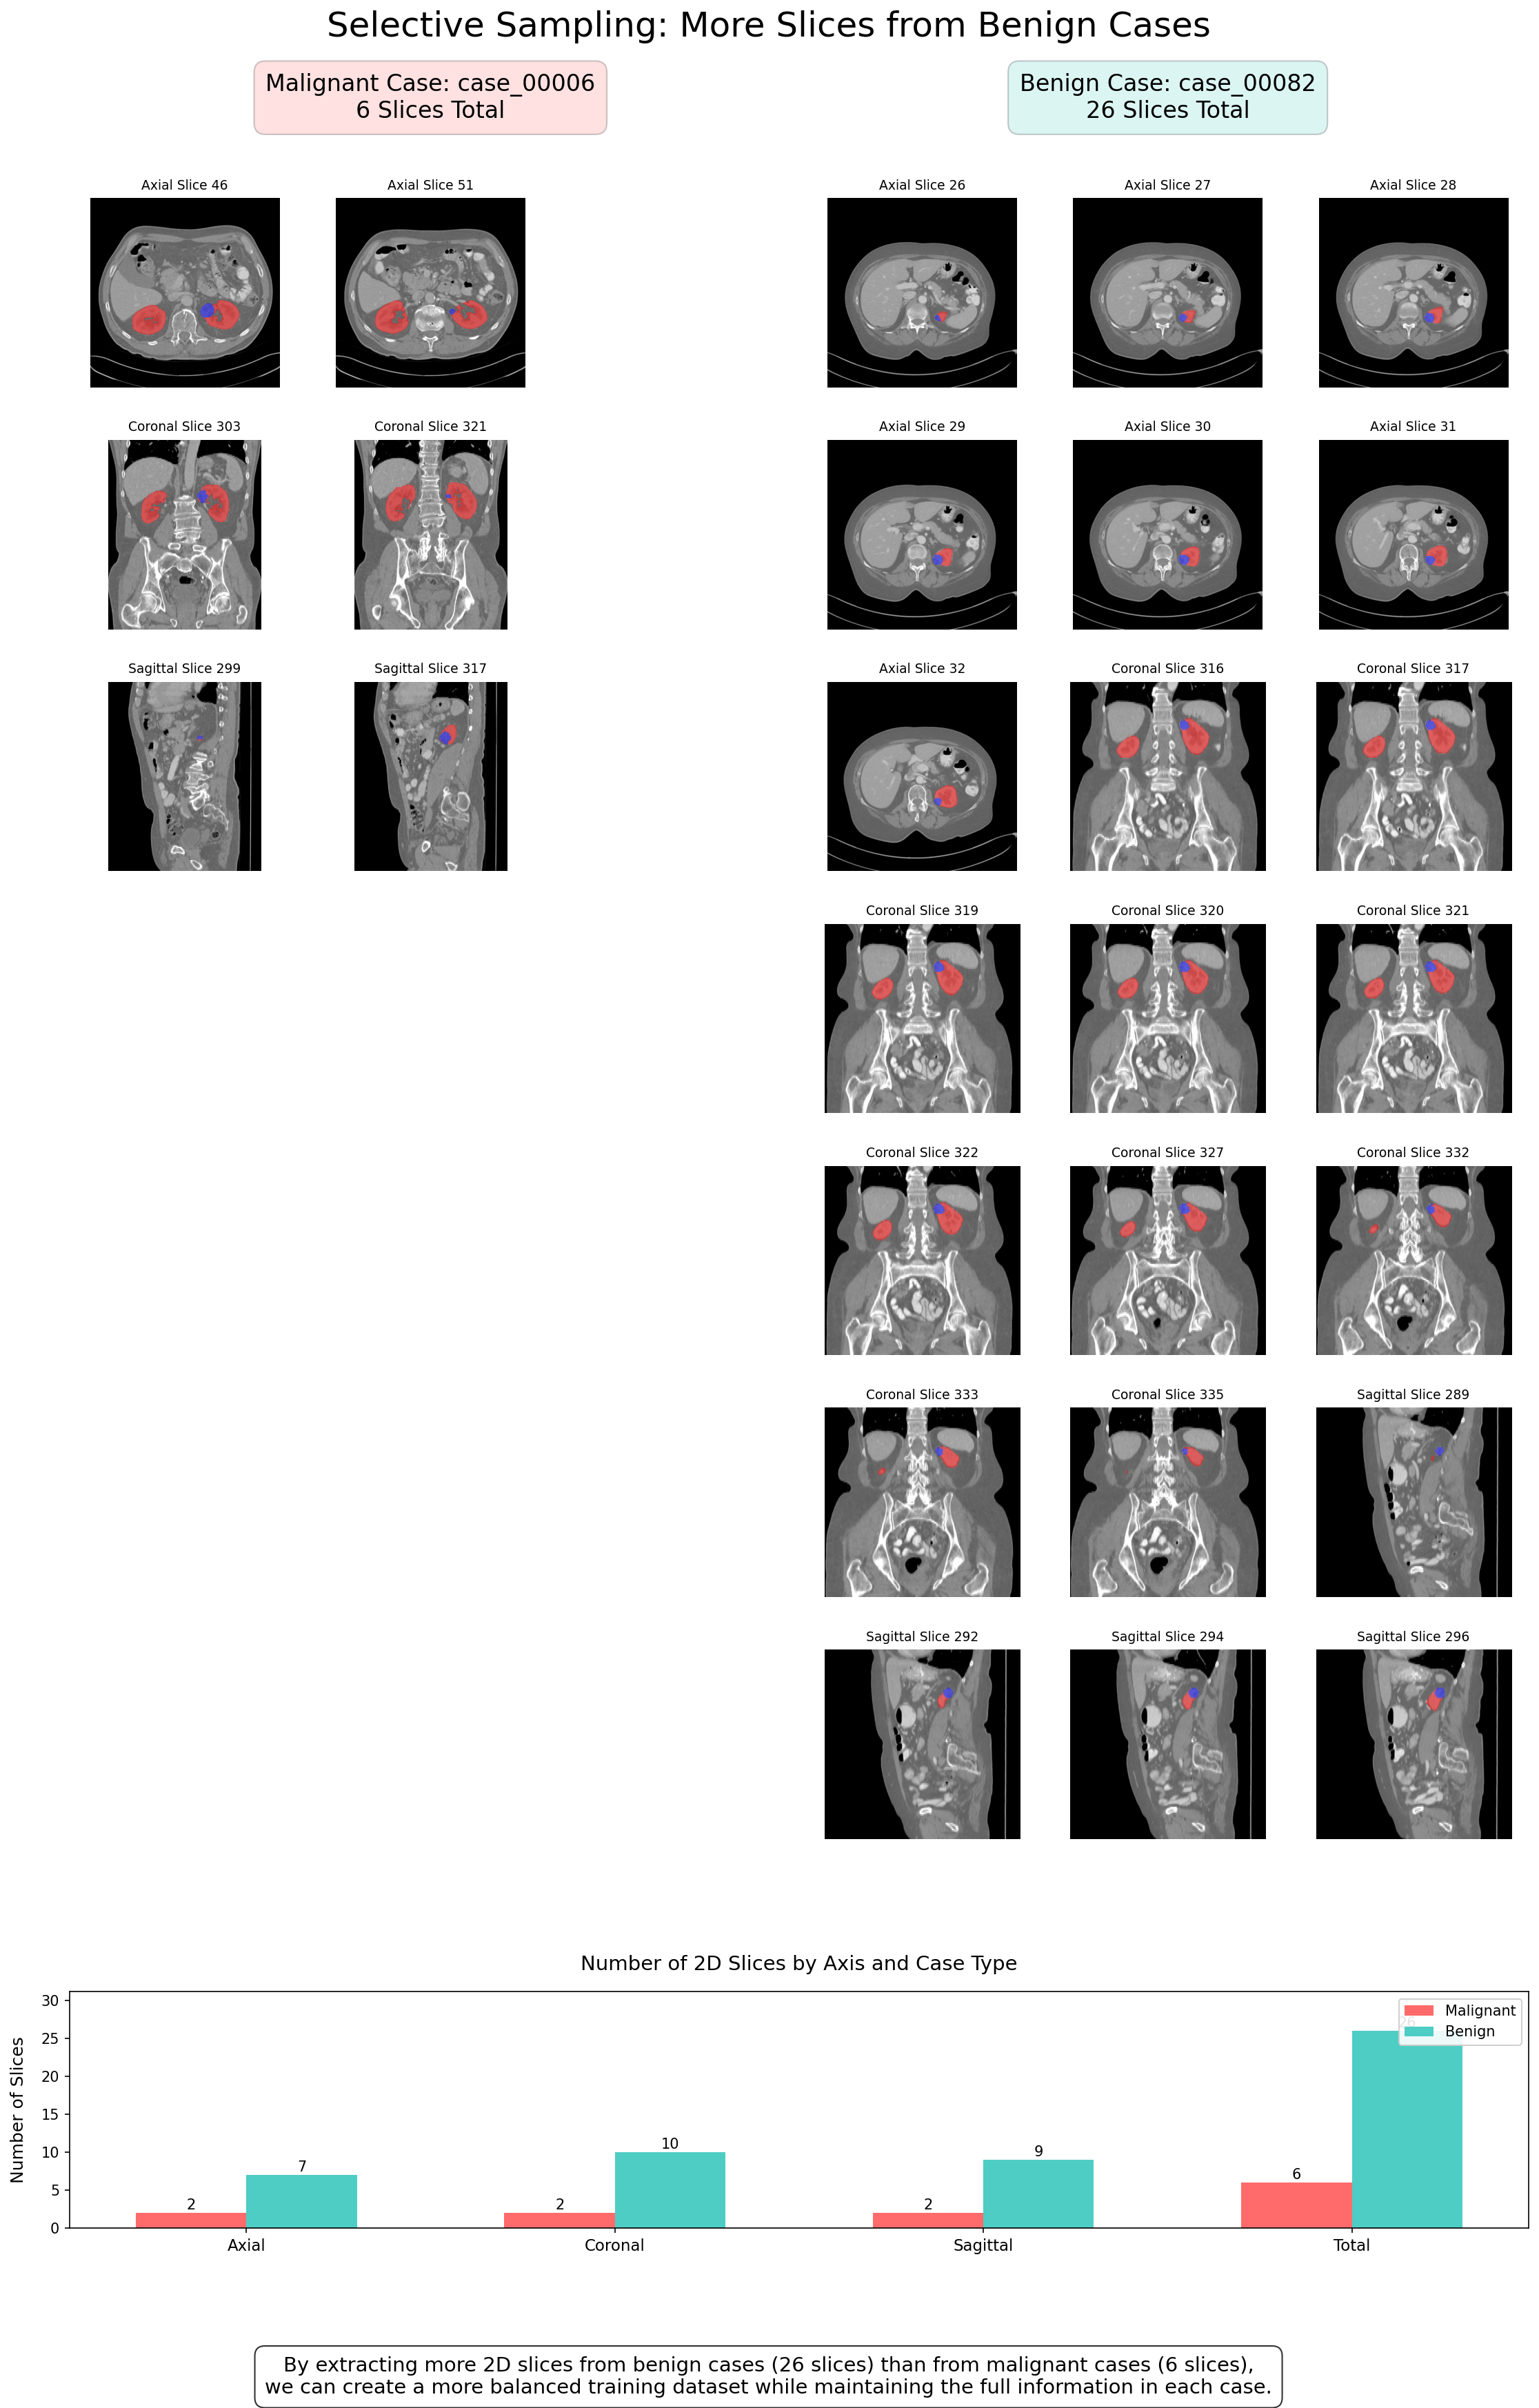

Balancing method using 2D slices

Our approach included several innovative components:

An additional advantage of our approach is that it provides the model with more diverse examples, showing tumors from different angles and enriching the information available for learning. This is analogous to training radiologists, who learn to identify diagnostic signs from different viewing angles.

Intelligent selective sampling method

This approach ensures that the model learns from the most information-rich examples, rather than random slices that might contain very little relevant information or not even show the tumor at all.